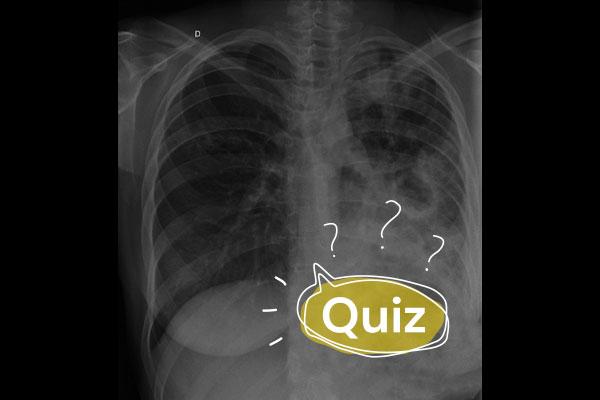

Mulher, 64 anos, com histórico de DPOC tabágico (carga tabágica de 120 maços-ano), GOLD E e hipoxêmica crônica, apresenta-se com o seguinte traçado eletrocardiográfico.

Qual o diagnóstico mais provável?

AIAM sem supra de ST.

BMiocardite viral

CCor pulmonale

DPericardite aguda